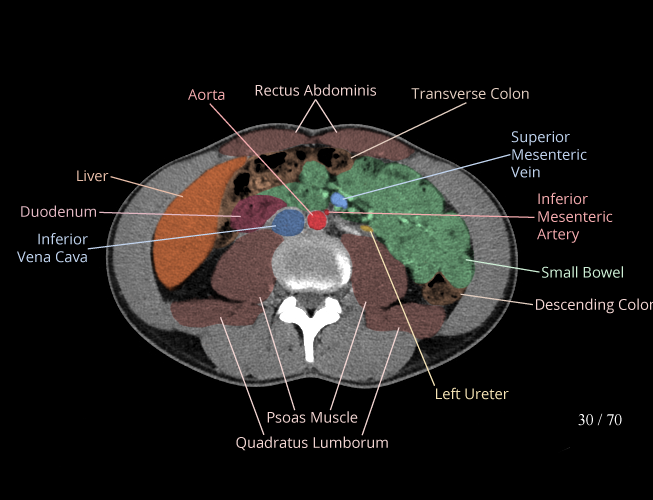

Body

Covers abdominal CT anatomy.